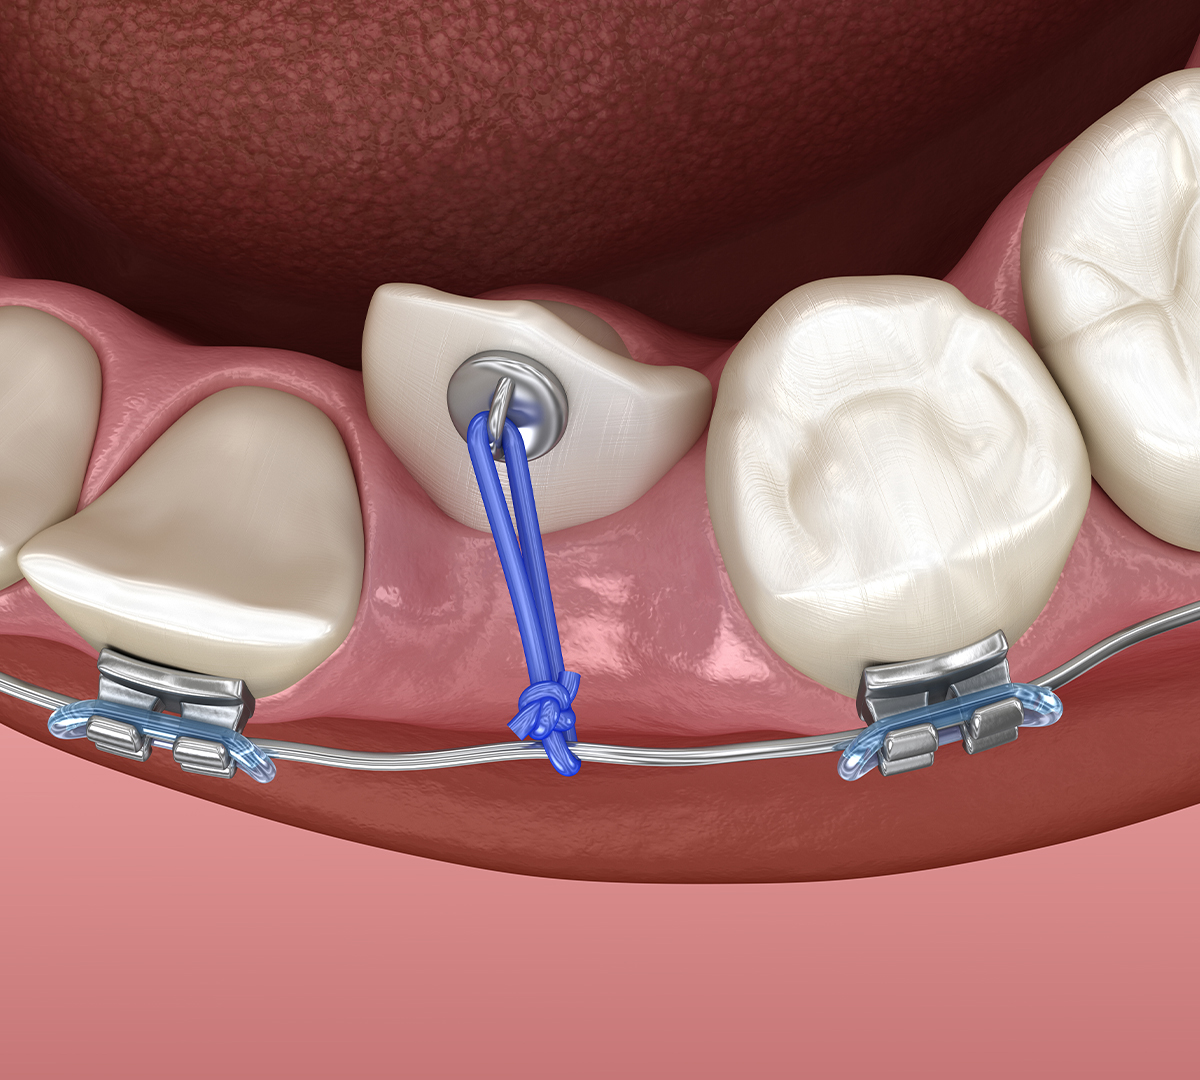

Dans le cas des canines incluses, un dégagement peut être réalisé pour faciliter leur éruption, souvent en association avec un traitement orthodontique permettant de guider la dent jusqu’à sa position correcte.

- Pour une canine incluse, la dent est dégagée et un dispositif de traction orthodontique peut être mis en place.